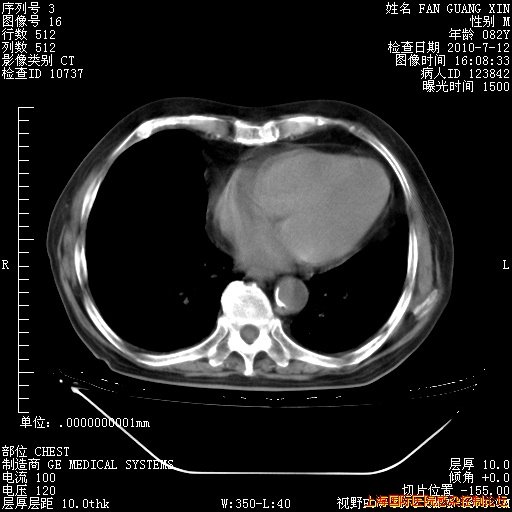

今天复查CT

今天CT

整整相隔30天的肺部CT好像有所好转啊。甲强龙减量第3天,需要观察体温。